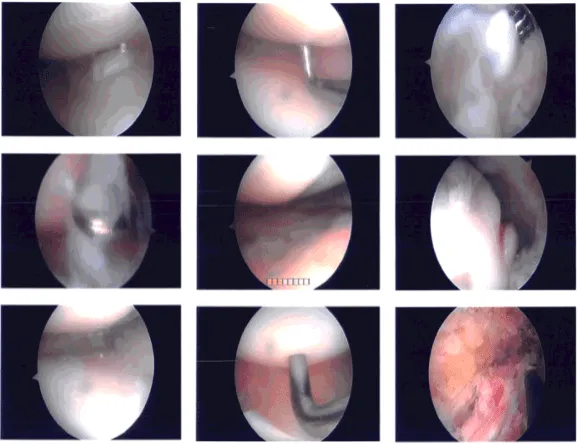

Examination showed intact medial and lateral meniscus as well as intact medial and lateral compartment. There were grade 3 to grade 4 osteoarthritic changes in the trochlea as well as patella. The lateral surface of the patella was denuded cartilage.

There was an osteophyte over the medial femoral condyle which was excised with the use of shaver and burr. Shaver was used to perform chondroplasty. The Coblation wand was also used to perform the chondroplasty. The patellar maltracking could be seen. Decision was taken for lateral release.

Arthroscope was entered through the medial portal and Coblation wand from the lateral portal. Lateral release of the capsule was performed from proximal to distal. All the bleeders were cauterized. Tourniquet was released at the end of the procedure. There was no active bleeding.

Intraoperative photo

After discussing treatment options, we have decided to proceed with formal physical therapy as well as a home exercise program for rehabilitation of the knee. We went over the arthroscopic pictures and removed the stitches during today’s visit.